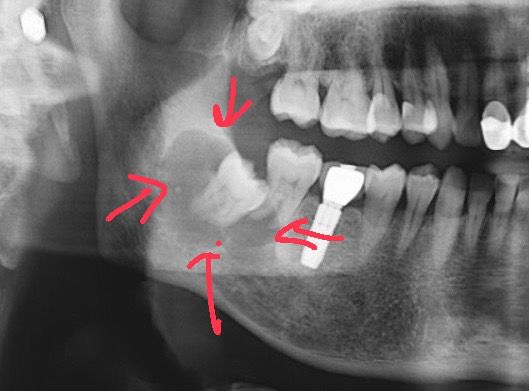

66歲張先生例行洗牙時,影像檢查發現未萌發的智齒周圍有3至4公分囊腫,造成周圍骨頭嚴重破壞(箭頭處)。 圖片來源:蔡承熹醫師提供

蔡承熹說,文獻指出,智齒未盡早拔除,有3%比例會在智齒周圍產生囊腫(俗稱水瘤)或良性腫瘤,一開始通常沒有症狀,卻會逐漸破壞骨頭,等到感覺疼痛腫脹,往往範圍已經很大,須全身麻醉才有辦法手術處理。